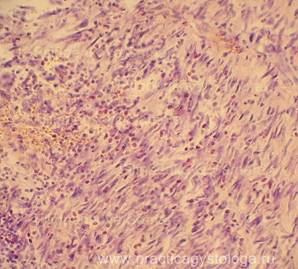

Рис. 3, 4. Стенка тонкой кишки значительно утолщена за счёт выраженного разрастания рыхлой соединительной ткани с умеренной-выраженной пролиферацией фибробластов, наличием лимфоцитов, диффузно расположенными эозинофилами в большом количестве. Окраска: гематоксилин-эозин. Увеличение х100 и х250.

Рис.5-10. Брыжейка тонкой кишки. Стенки сосудов брыжейки резко циркулярно утолщены за счёт склероза, часть сосудов с выраженной картиной продуктивного эндоваскулита. Окраска: гематоксилин-эозин. Увеличение х100 и х250.